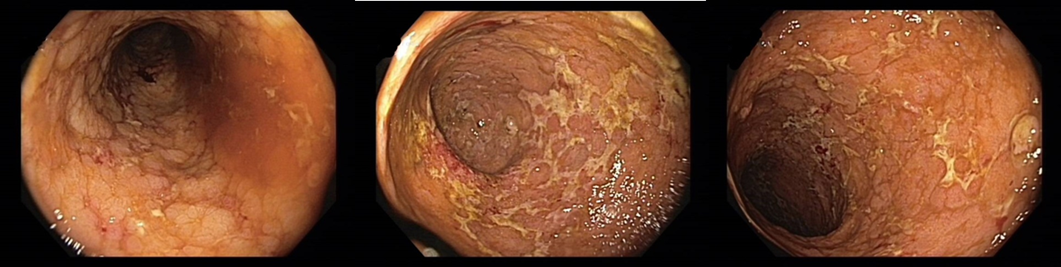

Koloskopie 2012/2: Endoskopický obraz Crohnovské pankolitidy, středně těžké až těžké (více je postižen P tračník), normální terminální ileum

2013/11 endoskopický obraz těžké pankolitidy charakteru Crohnovy choroby   - obraz cobble stones relativně je ušetřeno rektum, kde je ložiskově patrná   podslizniční cévní kresba

Koloskopie: Endoskopický kolitidy s ušetřením rekta, maximálním postižením v P tračníku – dle obrazové dokumentace zlepšení ve všech etážích tračníku   (i v P tračníku rozsah ulcerací snížen cca o 50%)